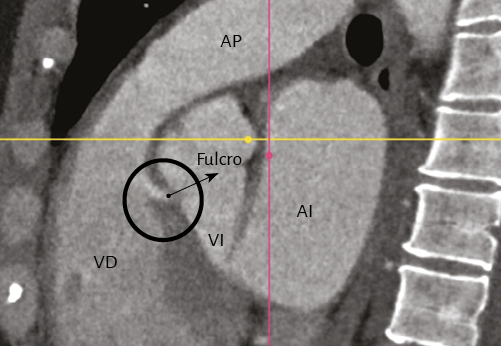

Imágenes del fulcro cardíaco. Los corazones de bovino, estudiados con tomografía computada (figuras 58-60), resonancia magnética (figuras 61 y 62) y radiología simple (figura 63) evidenciaron el núcleo osteo-condroide hallado en la disección, observándose la misma morfología y tamaño análogo. En la tomografía humana hemos encontrado, en el análisis de la región donde se encuentra el fulcro cardíaco a través de las disecciones realizadas, la presencia de una intensidad en unidades Hounsfield por encima de 110 UH, mientras que el músculo adyacente tiene unidades por debajo de 80 UH. De esta manera, en la imagen, la estructura del fulcro alcanza un promedio de 132 ± 4,5 HU. En las áreas adyacentes, correspondiente al músculo miocárdico, este valor se ubicó entre 47,96 ± 12,5 y 77,59 ± 21,64 HU (figura 64).

Figura 64. Tomografía computada en un paciente en la que se evidencia el fulcro cardíaco.

Nuestras investigaciones han demostrado, en el trayecto del segmento septal del anillo aórtico que se extiende desde el trígono izquierdo al derecho, la presencia de un núcleo sólido que hemos denominado fulcro cardíaco (por debajo del origen de la arteria coronaria derecha), donde se amarra el miocardio continuo en su inicio y al final, que como todo músculo necesita un apoyo para cumplir con su función.